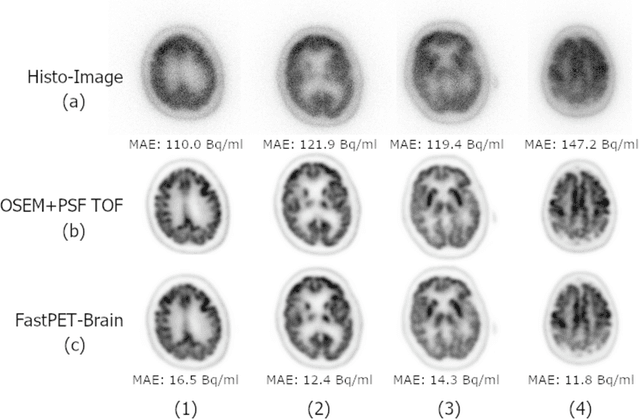

Abstract:Direct reconstruction of positron emission tomography (PET) data using deep neural networks is a growing field of research. Initial results are promising, but often the networks are complex, memory utilization inefficient, produce relatively small image sizes (e.g. 128x128), and low count rate reconstructions are of varying quality. This paper proposes FastPET, a novel direct reconstruction convolutional neural network that is architecturally simple, memory space efficient, produces larger images (e.g. 440x440) and is capable of processing a wide range of count densities. FastPET operates on noisy and blurred histo-images reconstructing clinical-quality multi-slice image volumes 800x faster than ordered subsets expectation maximization (OSEM). Patient data studies show a higher contrast recovery value than for OSEM with equivalent variance and a higher overall signal-to-noise ratio with both cases due to FastPET's lower noise images. This work also explored the application to low dose PET imaging and found FastPET able to produce images comparable to normal dose with only 50% and 25% counts. We additionally explored the effect of reducing the anatomical region by training specific FastPET variants on brain and chest images and found narrowing the data distribution led to increased performance.